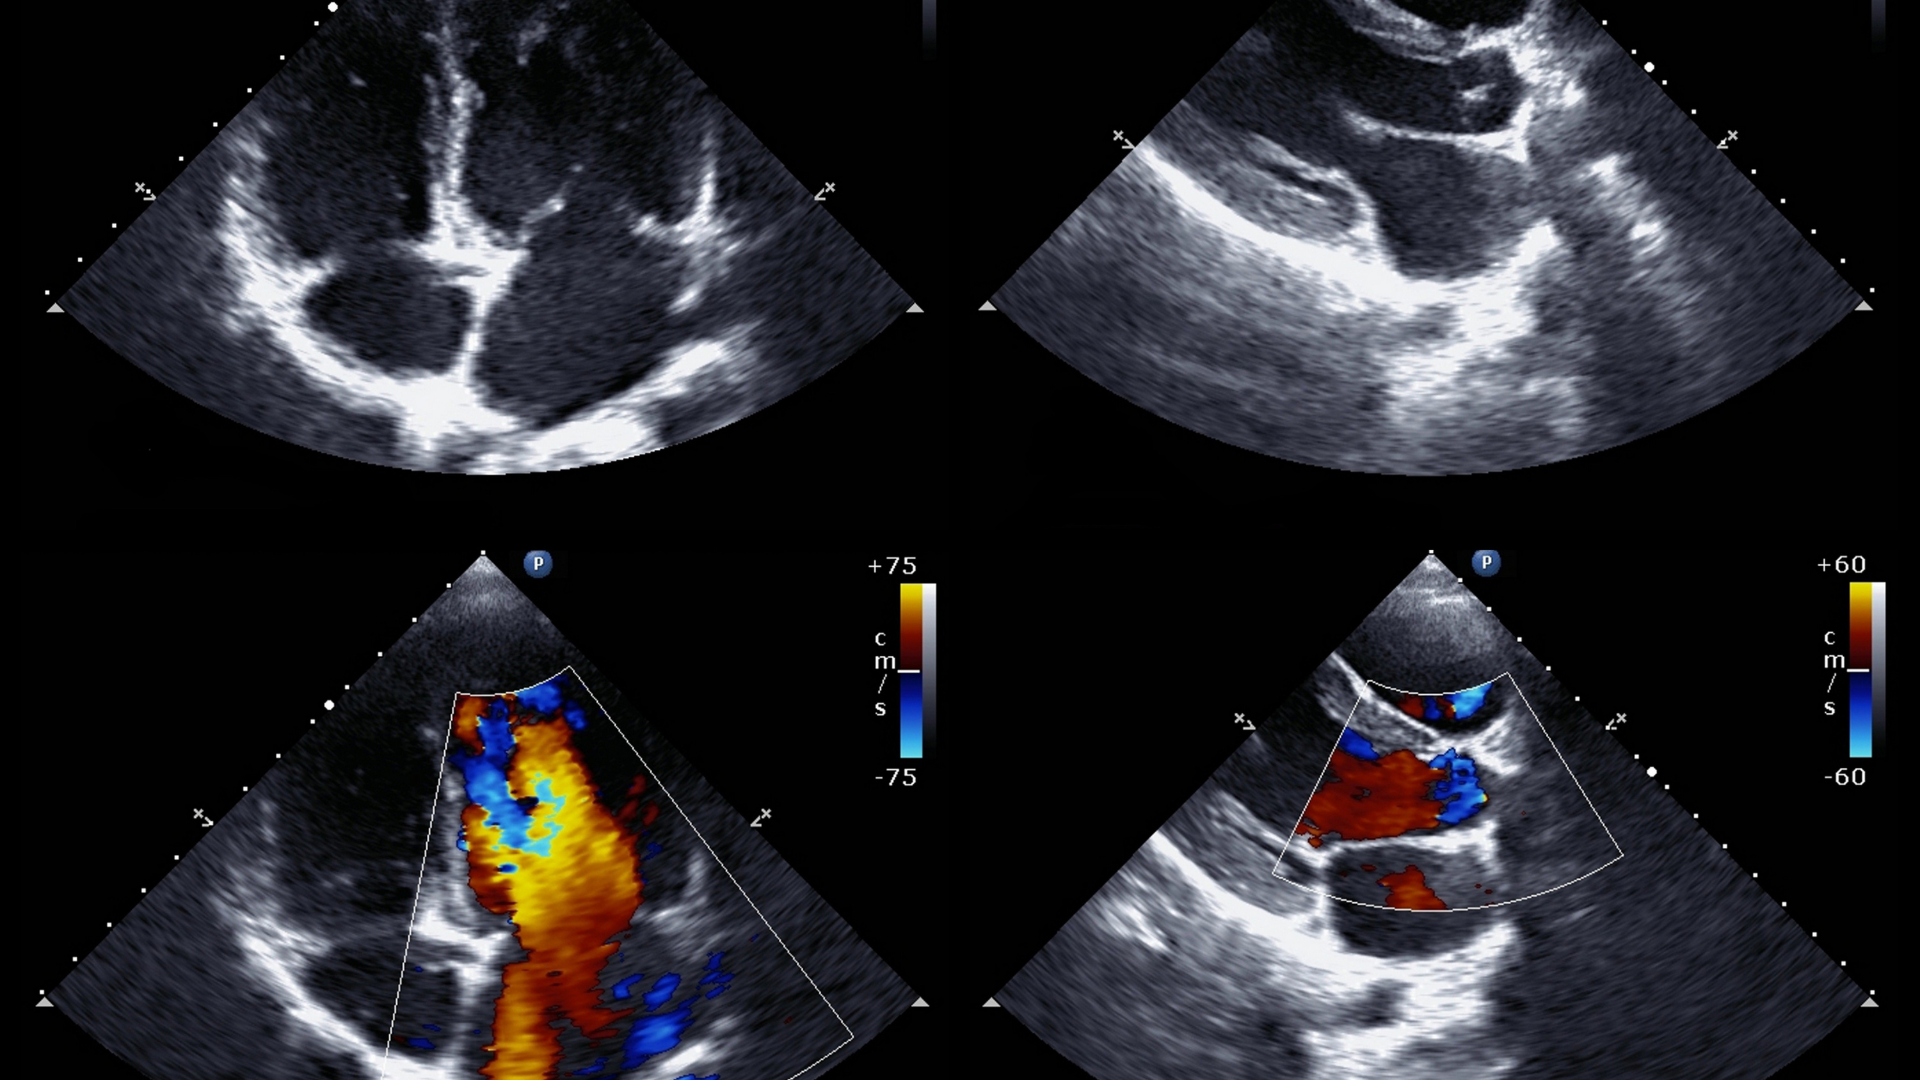

An echocardiogram, often referred to simply as an echo, is a vital diagnostic tool in cardiology. This non-invasive procedure uses ultrasound technology to create detailed images of the heart, allowing physicians to observe the heart’s structure and function in real-time. By emitting high-frequency sound waves, the echocardiogram provides a clear picture of the heart’s chambers, valves, walls, and the blood vessels attached to it. This helps in assessing overall heart health and diagnosing various conditions.

The echo can detect issues like stenosis (narrowing of valves) or regurgitation (leaking valves), ensuring timely intervention.